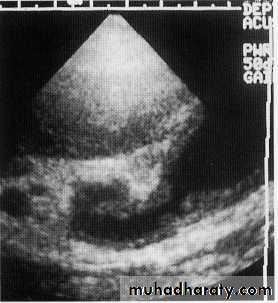

hydatid cyst